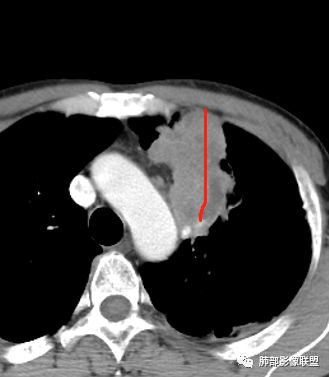

1.左肺上叶尖后段体积变化不大,病灶长轴沿支气管血管束向肺门侧生长,

2.病灶外围大,内带小,外朝内蔓延

3.病灶边缘以收缩为主,局部稍膨隆,

5.病灶内血管部分走形自然,部分走形僵直、粗细不均,提示病灶有部分破坏力,但是不强;

6.病灶与纵隔胸膜呈“糊墙”样改变,倾向炎性病灶;